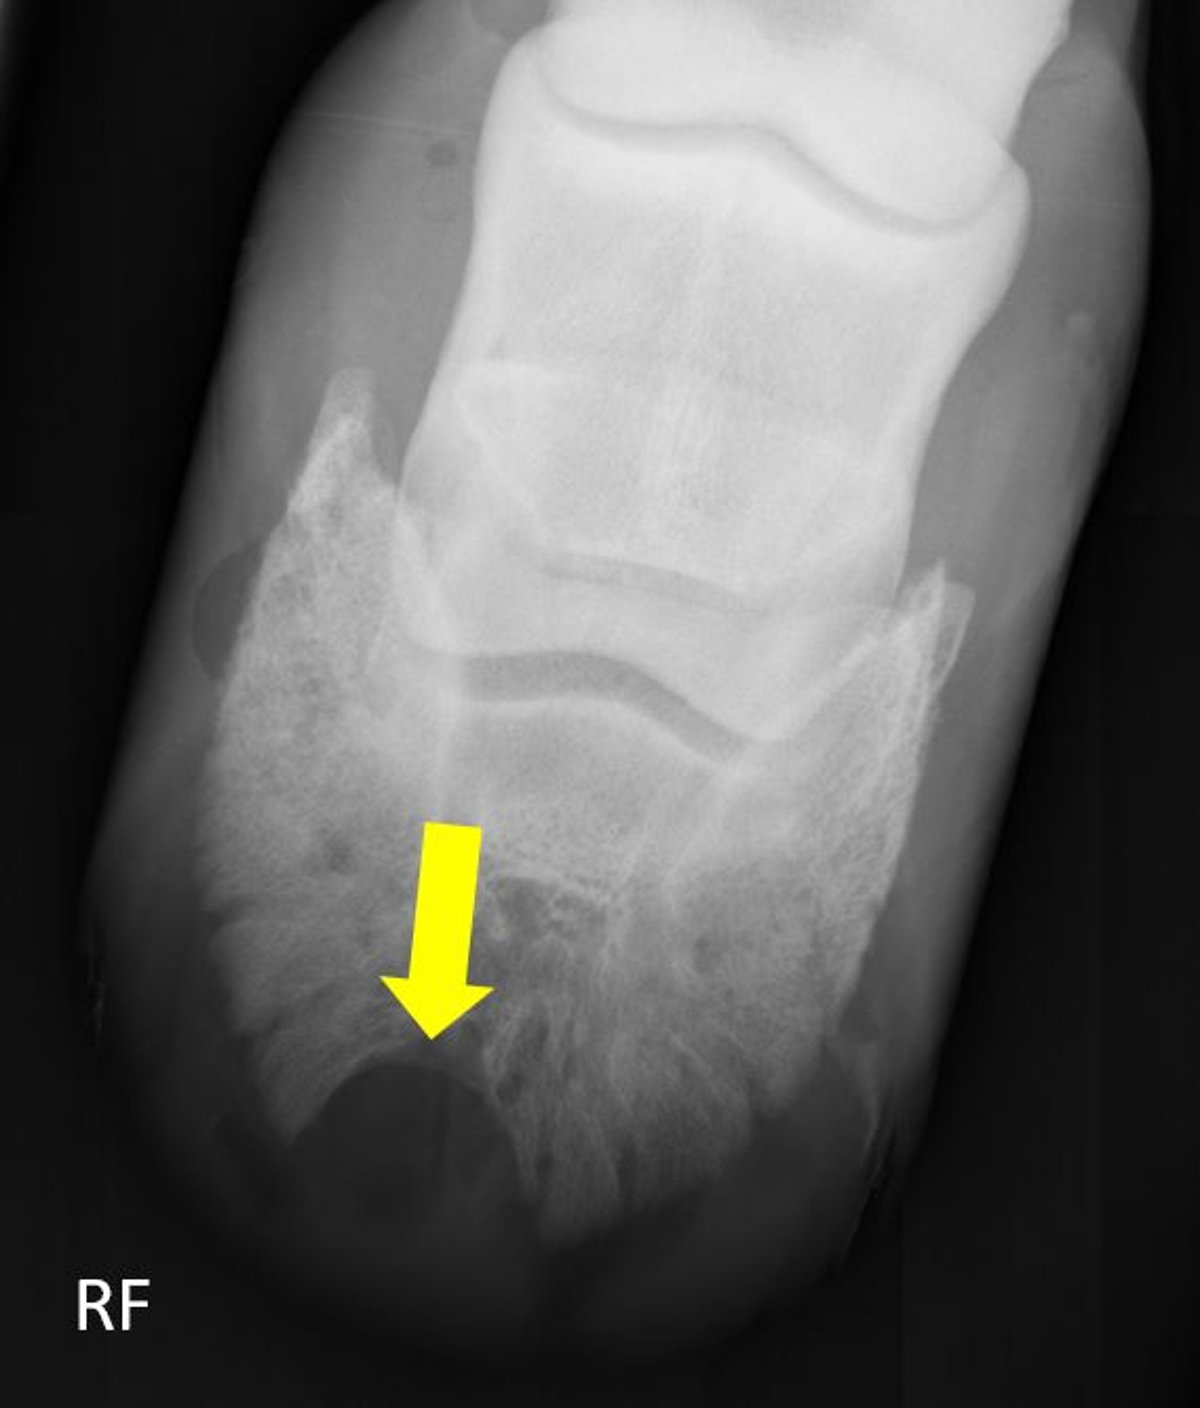

Radiograph showing a keratoma in the distal phalanx of a horse, represented by the large area of smooth, bony resorption at the dorsolateral aspect of the distal phalanx (arrow). This is a characteristic radiographic finding of a keratoma.

Courtesy of Dr. Valerie J. Moorman.